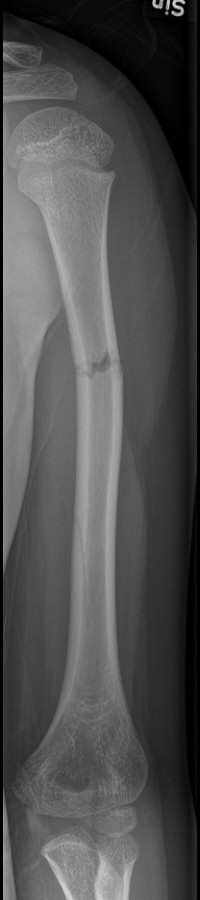

Skada barn: Fraktur humerusdiafys (barn)

1-årigt barn med diafysär humerusfraktur, fick vadd runt armen och linda runt kroppen i 3 veckor, därefter kliniskt läkt.